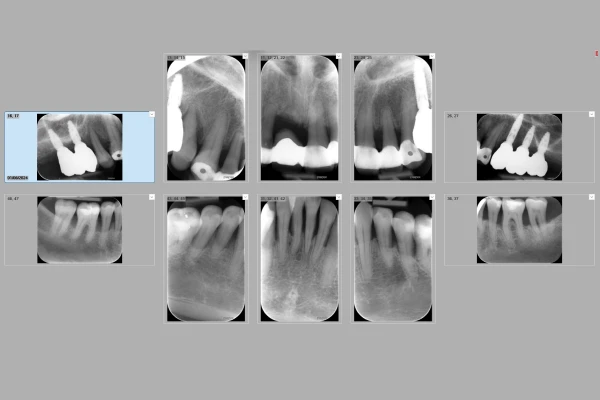

Technologies du cabinet B des Drs Bezzina, Biens, Stefan & Sabot à Nice : bilan rétro-alvéolaire numérique

Bilan rétro-alvéolaire numérique

Le bilan rétro-alvéolaire numérique permet une analyse précise des structures dentaires et osseuses. Grâce à cette technologie, le diagnostic des maladies parodontales est amélioré, permettant des traitements ciblés et efficaces. Cette méthode non invasive assure un confort optimal pour le patient tout en offrant des résultats détaillés et fiables pour le praticien.